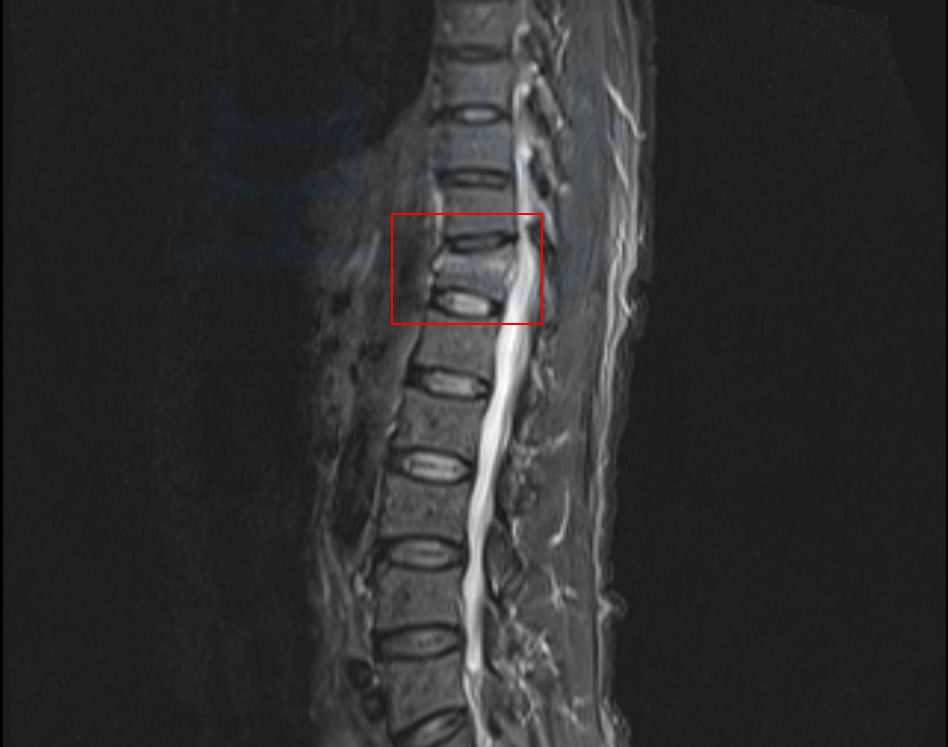

보상파트너로 문의해셨던 교통사고 당해 흉추12번 허리뼈 골절된 임@@님 또한

mri 촬영하니 허리뼈 골절 진단을 받게 되었고 약 약 4주간의 안정을 취해야 했습니다.